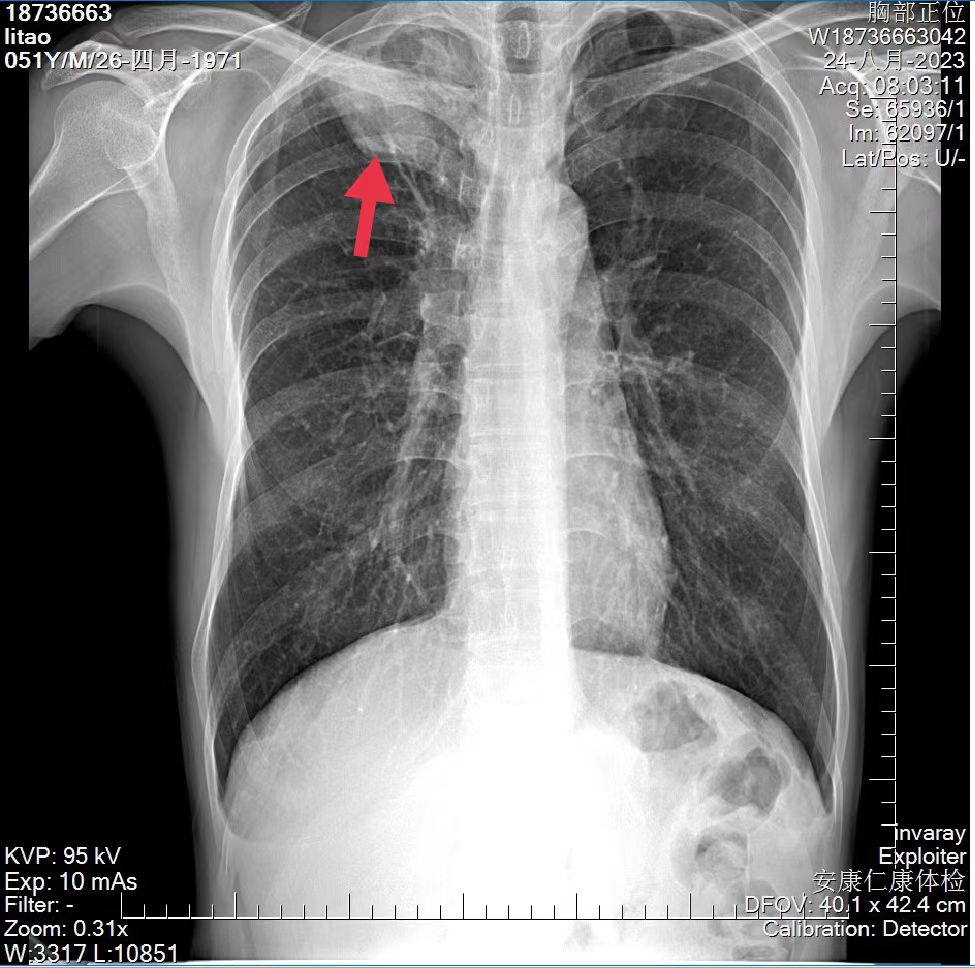

03、**男士,50岁

2023年8月20日在安康仁康体检部体检,胸部正位片提示:右肺尖可见团块状影,大小约6.3*4.0cm;腹部彩超提示:肝右叶可探及4.3*3.8cm中等回声包块,及时通知客户到三级医院进一步检查。于2023年8月28日首次回访,客户在西安某医院住院治疗,2023年9月10日跟踪回访,客户转诊至安康市中心医院住院治疗,病检结果为肺部恶性肿瘤,因无法实施手术治疗,目前化疗中。